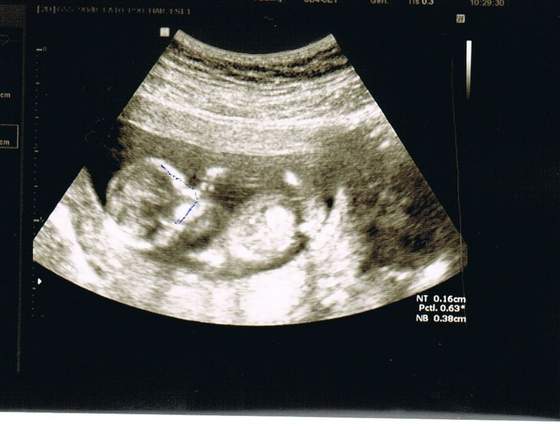

A to mój gigancioch, który ma już całe 71 mm. Zdjęcie troszkę niwyraźne, ale da się zobaczyć